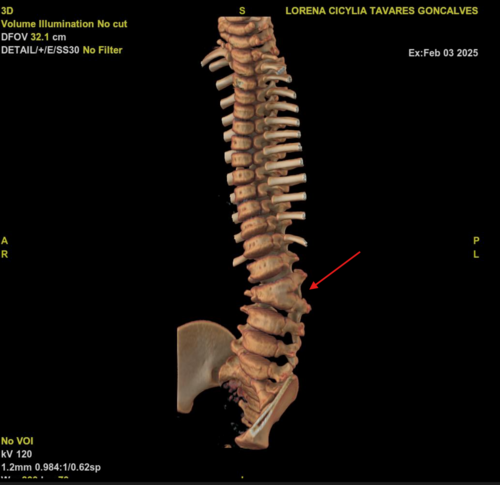

Sou mãe de uma menina, Lorena, de 2 anos e 8 meses, portadora das sequelas da mielomeningocele e chiari II, que está agora com o diagnóstico de escoliose, duas vértebras formaram-se juntas fazendo um formato de triângulo em meio a coluna, prendendo a medula e fazendo com que ela se curve rapidamente, por estar em fase de crescimento é uma cirurgia de emergência, pois quanto mais tempo passa mais a coluna se curva por conta do crescimento. Esta cirurgia tem uma espera muito longa via SUS e via judicial, por este motivo estamos tentando juntar o dinheiro do orçamento medico para fazermos o quanto antes.